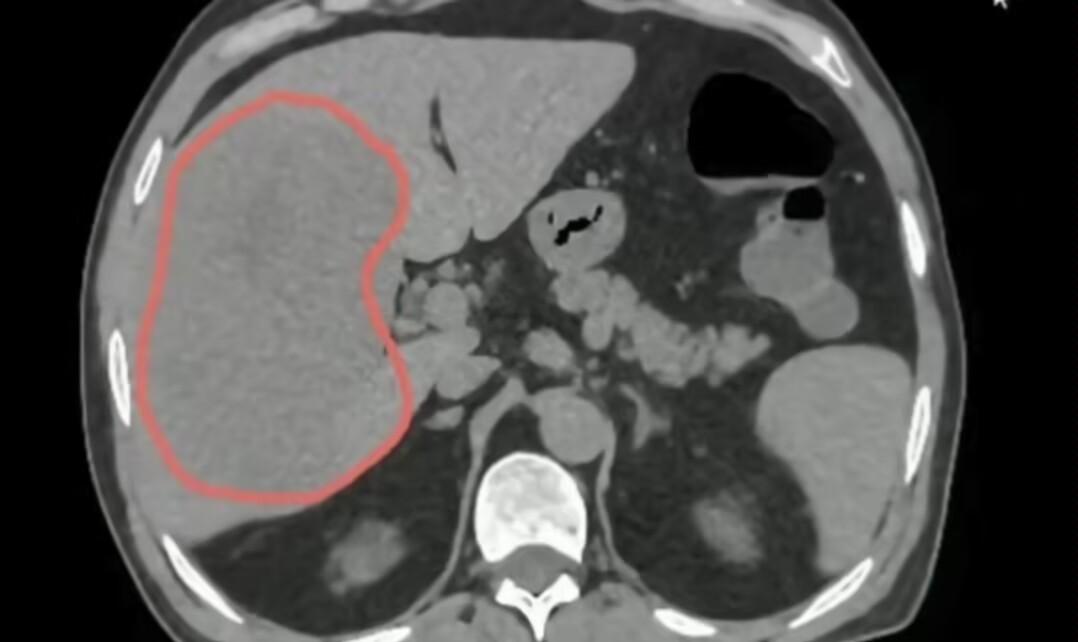

“医生,我转氨酶也不高啊,怎么会肝癌呢?”临床上的这位患者十分的不解,他体检看转氨酶也不高,以为是熬夜导致的,结果右上腹疼的受不了,综合检查后竟然确诊肝癌。

其实这样的案例不在少数,很多患者都有这样的一个误区:觉得转氨酶不高就没什么大事,殊不知,其实像肝硬化、肝癌这种病情,转氨酶可能会显示正常。

所以说,只盯着转氨酶这一项指标去看肝脏安不安全,会漏掉危险。

这也就是为什么,我们不能只靠这一项来判断肝脏健康。尤其是那些有危险因素的朋友们,即使转氨酶看着没事,也需要做一下影像学检查、病毒量、乙肝五项等,综合